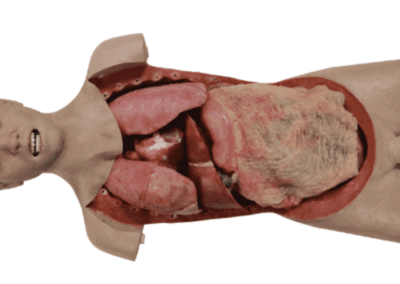

Modelos

Anatômicos

Ferramentas para estudo detalhado do corpo humano.